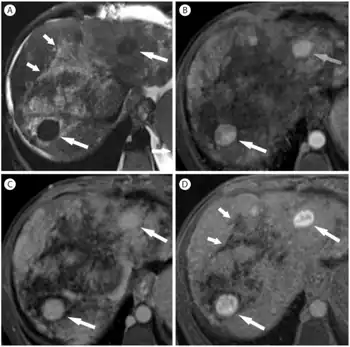

Large regenerative nodules and confluent fibrosis in female with Budd-Chiari syndrome-a)irregular hyperintense lesions b) nodules are homogenously hypervascular c)nodules remain hyperenhancing at 3 minutes delay d)hyperintense in the hepatobiliary phase